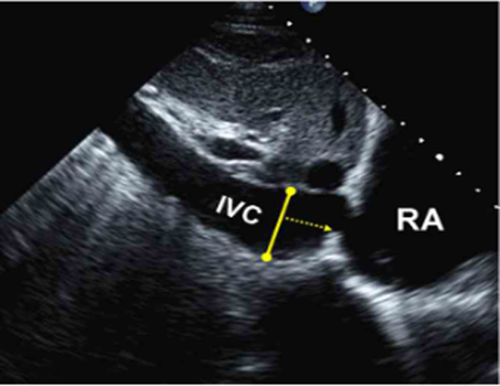

重症超声对休克患者的动态容量评估

重症超声动态观察下腔静脉进行容量评估